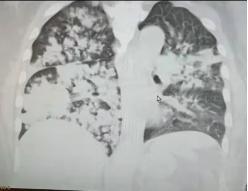

老喻入院时的肺部CT

近日,康复科与内科ICU、呼吸与危重症科、神经内科、营养科、中医科等MDT团队共同接诊一例急重症“脑出血后继发性吸入性肺炎”患者,经由MDT团队协作、不懈治疗,已解除患者生命危机,稳定控制生命体征,肢体功能恢复良好,独立行走出院。 10月12号上午,康复科接到内科ICU会诊一名48岁重症肺炎伴昏迷的男性患者老喻。老喻今年9月8日脑出血瘫痪后一直在当地医院治疗,10月1日饮石蜡油通便时将石蜡油误吸入肺中;CT检查双肺大面积炎,诊断为“脑出血,吸入性肺炎”收入我院内科ICU。内科ICU刘纯主任、张强主治医生迅速组织呼吸与危重症科刘备战主治医师、神经内科宋治主任医师、康复医学科李旭红主任、营养科刘红主治医师、中医科肖岚主任MDT团队会诊,完善相关讨论后患者有明显的康复介入指征。经过一个月呼吸机支持下的呼吸与排痰训练、肢体运动康复、体外膈肌起搏治疗、语音阀等康复技术治疗,老喻能脱呼吸机并于11月3日从内科ICU转至呼吸与危重症科普通病房。